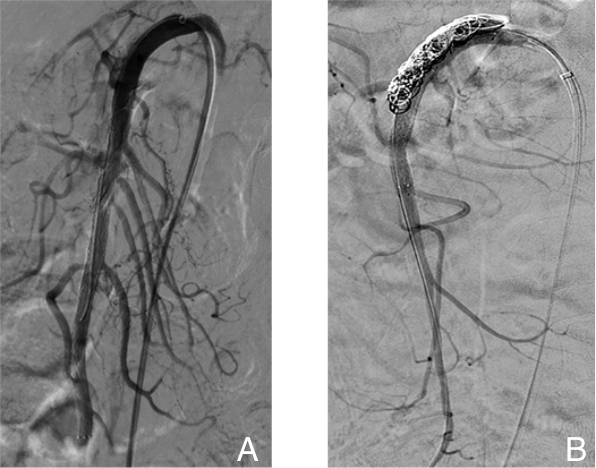

摘要:背景与目的 自发性孤立性肠系膜上动脉夹层(SISMAD)是一种较为常见的内脏动脉夹层疾病,主要表现为急性腹痛,严重者可引发肠缺血甚至坏死。随着CT血管成像(CTA)等影像技术的普及,SISMAD的检出率显著提高,但目前针对其治疗策略仍存在争议,尤其在保守治疗与腔内介入治疗之间的选择缺乏统一标准。为探讨两种治疗方式的临床效果及适应人群,本研究回顾性分析本中心SISMAD患者的临床资料,并比较不同治疗方式的短中期疗效,为制定个体化治疗策略提供依据。方法 回顾性分析2018年1月—2023年12月浙江省宁波市第二医院确诊的174例SISMAD患者临床资料,其中保守治疗30例,腔内介入治疗144例(包括支架植入和部分假腔弹簧圈栓塞联合支架植入)。术前均行CTA或肠系膜上动脉造影并分型。随访评估患者术后1个月和1年症状缓解情况及影像学指标,包括夹层重塑率、支架通畅性等。结果 保守治疗组1个月症状缓解率为90.0%,1年为92.8%;介入治疗组分别为99.3%和98.6%。1个月症状缓解率差异具有统计学意义(P=0.016),1年症状缓解率差异无统计学意义(P>0.05)。分型亚组比较中,介入治疗组各型症状缓解率普遍高于保守治疗,但差异均无统计学意义(均P>0.05);保守治疗组Ⅲ型患者症状控制较差,出现死亡病例。介入治疗成功率为99.3%,1年内支架移位或闭塞为0例,完全重塑率为86.8%,支架通畅率为100%。部分患者支架内出现少量附壁血栓,未见血流阻断。结论 腔内介入治疗对SISMAD患者具有较高的技术成功率和良好的短中期疗效,尤其适用于真腔血流受限的Ⅱ型及Ⅲ型患者。建议根据夹层分型及血流受限程度,个体化制定治疗方案,以提升疗效、降低风险。